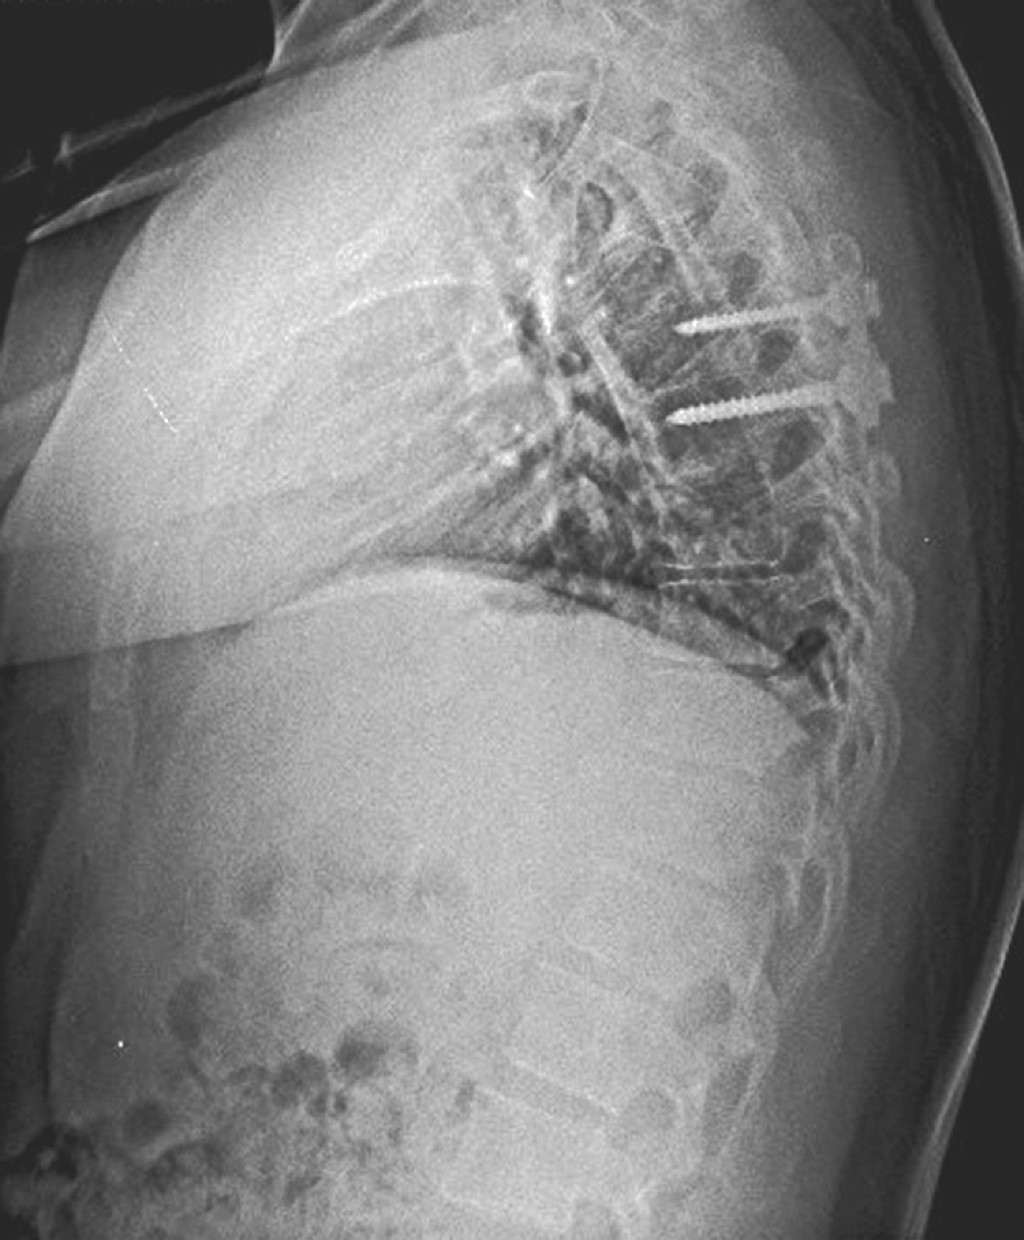

Se decide efectuar manejo quirúrgico mediante discectomía con abordaje posterolateral transfacetario y uso de microscopio, así como instrumentación unilateral del segmento. La técnica quirúrgica consiste en colocar al paciente en posición de decúbito prono con soportes laterales. Con uso de monitoreo neurológico intraoperatorio se hace una incisión cutánea de aproximadamente 5 cm, disección subcutánea, incisión de la fascia y musculatura a un lado de la línea media. Hemilaminectomía ipsilateral con resección facetaria parcial. Bajo visión microscópica se realiza discectomía y por último, fijación unilateral del segmento con tornillos transpediculares.

Se dio seguimiento al paciente en consulta externa cada dos semanas, el cual presentó recuperación del compromiso neurológico a las ocho semanas, logrando una marcha de características normales, con adecuada fuerza y sensibilidad en miembros pélvicos, sin datos de compromiso medular (Figuras 3 y 4).

Figura 3

Figura 4